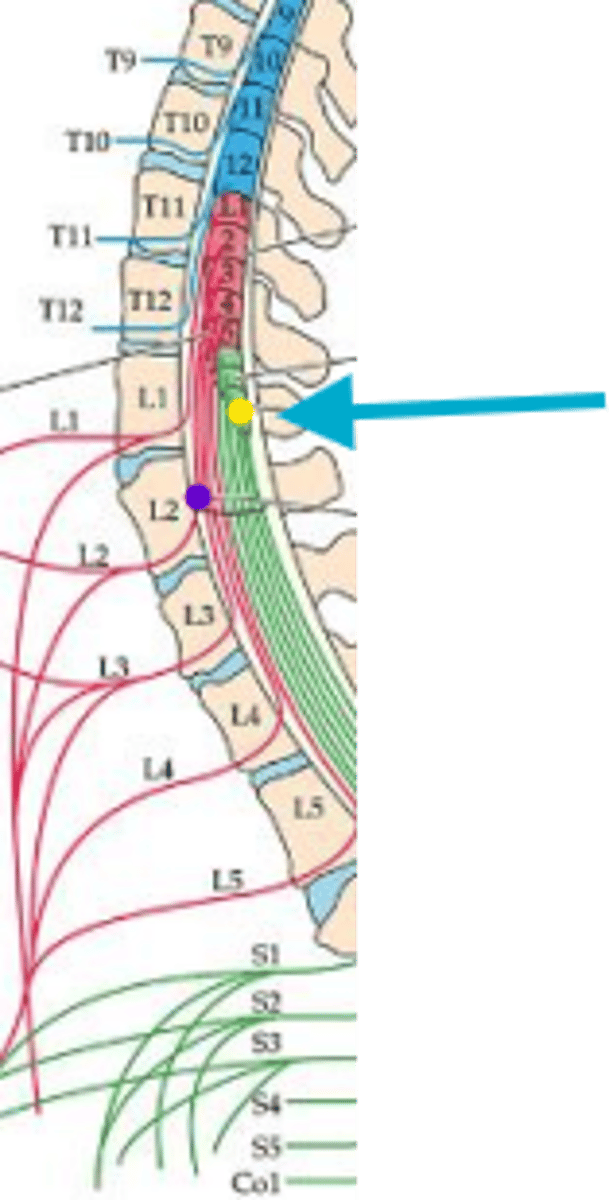

What space is the yellow arrow pointing to?

what space is the yellow arrows pointing to?

Name the structure the yellow dot is on.

what structure is the blue pin in?

What is number 50 or the blue dot?